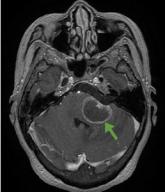

Central nervous system lymphoma mimicking Bell palsy